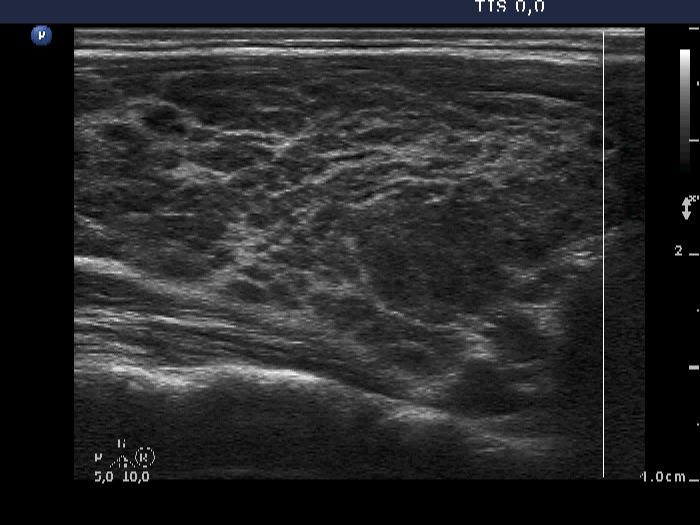

Case 467 (ultrasonographic picture 2)

Right lobe, longitudinal scan. Bundles of connective tissue divide the thyroid into smaller areas.